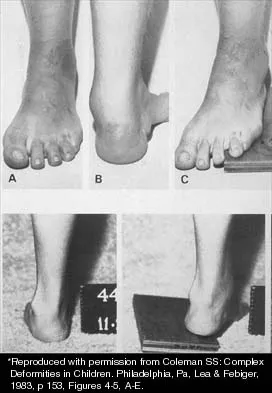

Question 78

A 15-year-old boy with a type I hereditary sensory motor neuropathy (Charcot-Marie-Tooth disease) reports recurrent ankle sprains and significant pain in the hindfoot and midfoot despite orthotic management. Examination reveals that he walks with a drop foot and has dynamic clawing of the toes. Clinical photographs of the left foot are shown in Figure 7. Management should consist of

Explanation